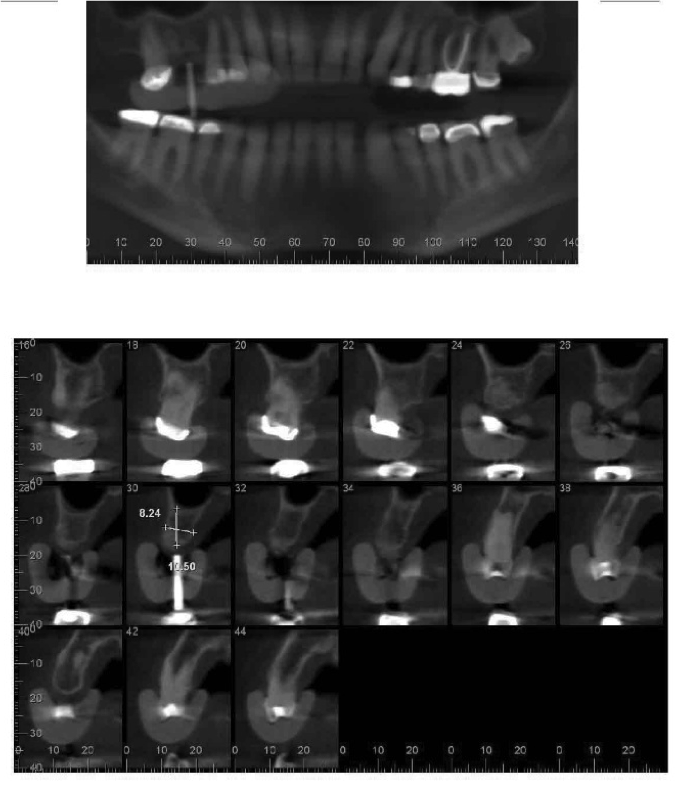

In this case, the patient’s right maxillary first molar had been extracted, and the site was grafted. The periapical radiograph taken after 6 months of healing indicated the presence of dense bone (Figure 11). There was also ample attached mucosa (Figure 12). Impressions were taken, a diagnostic cast was made, and a wax-up of the restoration was placed in the model (Figure 13). To make the radiographic guide for this case, a silicone putty index was created over the diagnostic wax-up, as described earlier. A panoramic radiograph and a CBCT scan (Figure 14) were taken with the radiographic guide in place; the guide post in the index can clearly be seen.

After merging the digitized cast and CBCT scan data, the dimensions of the site were evaluated. Almost 11 mm of bone was present below the maxillary sinus, and the width of the site was 8.5 mm, which was sufficient space to enable creation of a screw-retained restoration. To facilitate the screw access, a decision was made to position the implant slightly lingually, while maintaining the implant within the housing of buccolingual plate.

Additional planning steps are evident in Figure 15. The soft-tissue configuration has been sketched in white, with the planned implant position indicated in blue. The implant appears to avoid any impingement on the sinus floor or the adjacent roots, which are straight and parallel. The diameter of the planned implant was 4.8 mm, and the length was 8 mm. Although the length was somewhat short, the width was expected to compensate for that, along with the fact that a two-stage protocol would be followed. The planning procedures also provide valuation information about the drilling procedures for the osteotomy preparation.

Fig 14. Panoramic radiograph and CBCT scan taken with radiographic guide in place.

Figure 14

Fig 15. Imaging showing additional planning steps.

Figure 15